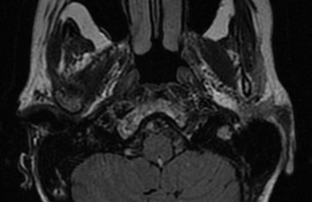

Clinique : à l’interrogatoire apparition depuis 2 à 3 semaine d’une baisse d’audition à droite, d’une diplopie horizontale, de difficultés à la marche avec déviation vers la gauche et plus récemment d’une diminution de la sensibilité du bord de langue droit, sans troubles de déglutition. Indice OMS à 1. A l’examen, présence d’adénopathies cervicales bilatérales et axillaires droites, signe de Rombergue présent, marche déviée à gauche, absence de syndrome cérébelleux. Masse abdominale palpable du flanc droit. Examen ORL retrouve une lésion de la paroi postérieur et latérale droite du cavum.

Classement LNH diffus à grandes cellules B stade IV atteinte ganglionnaire sus et sous-diaphragmatique, atteinte du cavum avec extension au conduit auditif droit, atteintes péritonéales, OMS = 1, LDH augmentées soit 2 facteurs selon IPIaa.

Décision : R-ACVBP x 4, prophylaxie neuro-méningée, recueil de CSP après 3ème cycle. Consolidation par 2 cycles de méthotréxate hautes doses, conditionnement BEAM autogreffe, sous réserve d’un lymphome chimio-sensible, radiothérapie sur la base du crâne et le conduit auditif droit

Evaluation 3 mois après fin de la radiothérapie :

- IRM du conduit auditif interne et encéphalique : stabilité de l’infiltration du CAI droit mesuré à 9 mm. Régression de la masse de l’angle ponto-cérébelleux droit ;

- Scanner TAP lésion péritonéale résiduelle taille 33 x 22 mm

Classement rémission complète incertaine

Surveillance : évolution favorable 2 ans après la fin du traitement